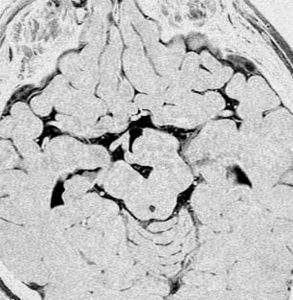

術後のMRIです,pterional approach でしか摘出できない腫瘍でした

高い位置がとどかず少し取り残しました

gelastic seizureは減荷されましたが残り,術後に視野欠損を後遺しました